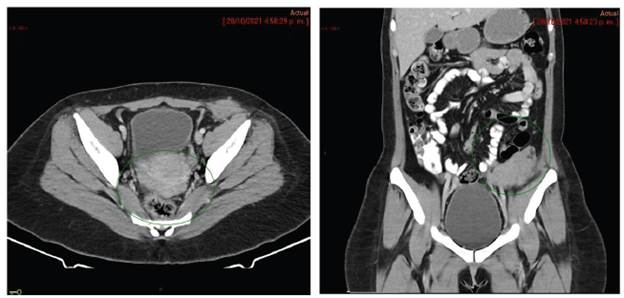

En diciembre de 2021 es valorada en junta de Ginecología Oncológica del INC con imágenes de RM institucionales realizadas una semana antes de la junta las cuales reportan masa que compromete la pared abdominopélvica izquierda a nivel extra e intra pélvica que contacta el borde antimesentérico del colon descendente y signos de carcinomatosis peritoneal (Figuras 1 y 2); la revisión institucional de patología reportó un Tumor de los Cordones Sexuales con Túbulos Anulares (TCSTA) por caracterización histológica e inmunohistoquímica la cual fue positiva para queratina AE1-AE3, inhibina, calretinina, CD56, CD99 (focal) y WT1; la inmunohistoquímica fue negativa para cromogranina y sinaptofisina. El índice KI 67 fue del 10 %. En esta junta se define llevarla a cirugía citorreductora, que es llevada a cabo el 11 de enero de 2022, y se realiza citorreducción vía abierta que incluye histerectomía, salpingooforectomía bilateral, peritonectomía de cúpula diafragmática derecha, peritonectomía parietal derecha flanco y fosa iliaca derecha, peritonectomía pélvica anterior y posterior, resección anterior baja de recto con anastomosis colorrectal, omentectomía supracólica, resección local amplia de pared abdominal de flanco y fosa iliaca izquierda con resección de cicatriz sobrelínea media, resección del ligamento redondo, fulguración y resección de implantes peritoneales en meso del íleon distal, resección del ligamento de treitz. Se calcula Índice de Carcinomatosis Peritoneal (ICP) en 18; este índice tiene un valor mínimo de 0 y máximo de 39, se utiliza para evaluar la cantidad y la distribución de la enfermedad tumoral en el peritoneo 9.